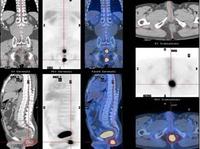

(五)CT檢查由於CT具有對軟組織腫瘤的密度分辨力和空間分辨力的特點,用來診斷軟組織腫瘤也是近年常用的一種方法。

(六)MRI檢查用它診斷軟組織腫瘤可以彌補X線CT的不足,它從縱切面把各種組織的層次同腫瘤的全部範圍顯示出來,對於腹膜後軟組織腫瘤、盆腔向臀部或大腿根部伸展的腫瘤、膕窩部的腫瘤以及腫瘤對骨質或骨髓侵襲程度的圖像更為清晰,是制訂治療計畫的很好依據。